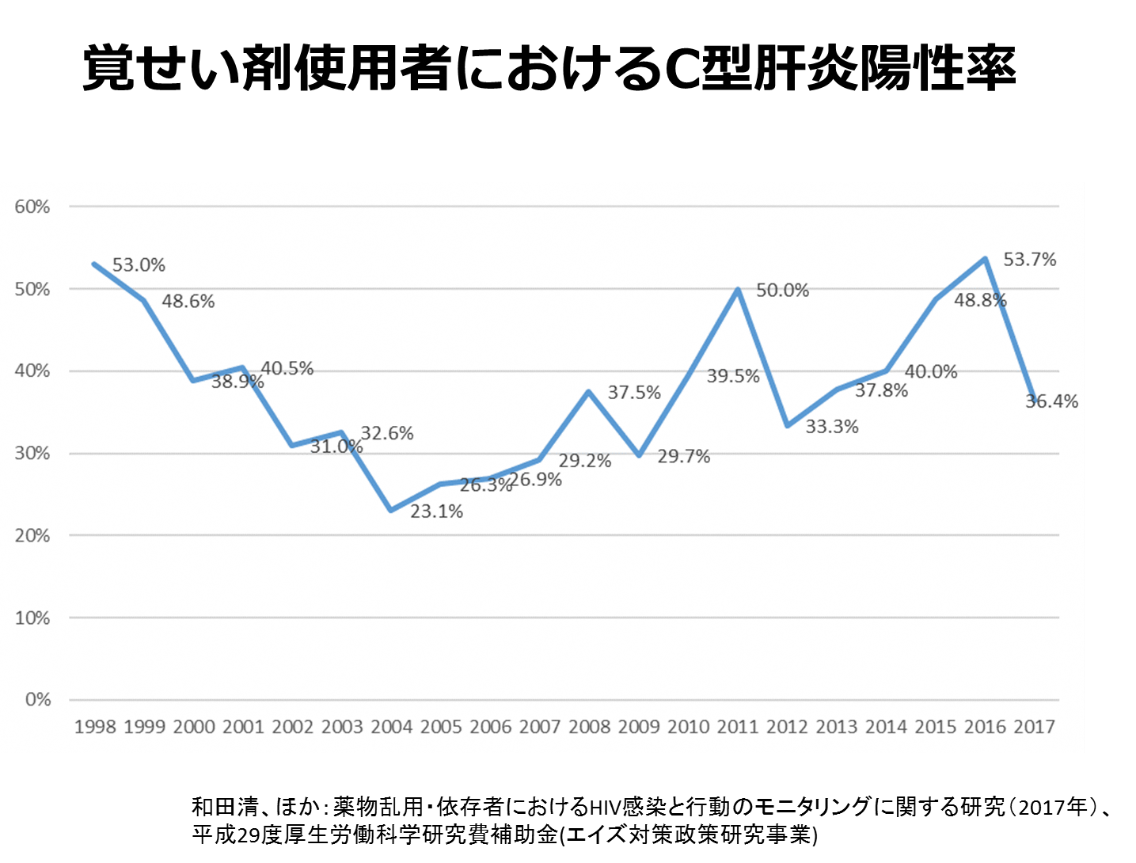

市民に広がる覚せい剤の恐怖 佐賀県警察本部